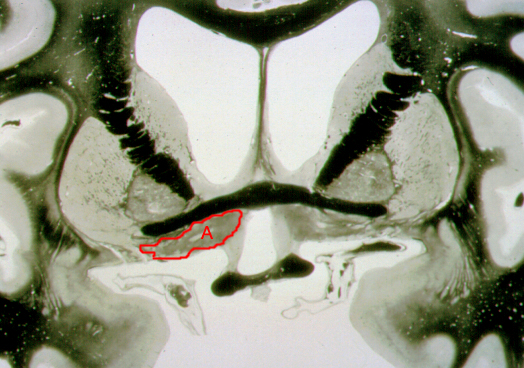

What is structure “A”?

Nucleus basalis of Meynert

Which area has extensive neuronal cell death due to Alzeheimer's disease?

Amygdala

Nucleus accumbens

Septal nuclei

Thalamus